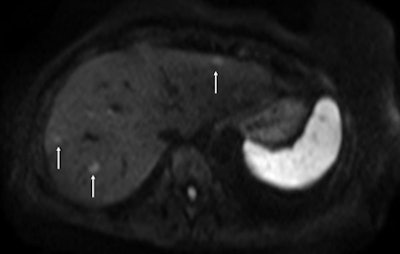

Fat-suppressed T2-weighted fast spin-echo MR image obtained in 61-year-old man with liver metastases from colorectal cancer. Only one metastasis in the right liver lobe is seen on this slice (arrow). Moreover, this lesion is barely seen because it is located next to a vessel. Images courtesy of Dr. Valerie Vilgrain.